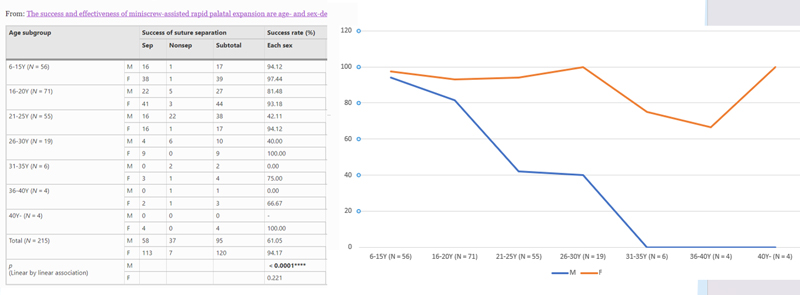

However, MARPE / MSE can be successful at any age, but the ideal age for treatment is typically during adolescence when the upper jaw suture is growing and developing. Studies have shown that MARPE can be more effective in Female adults when compared to male adults.

In one study with 215 patients, the success rate for female patients was 94% compared to 61% for male patients (REF). This difference was more obvious in male patients older than 25. However, male patients younger than 20 have almost the same success rate as female patients.